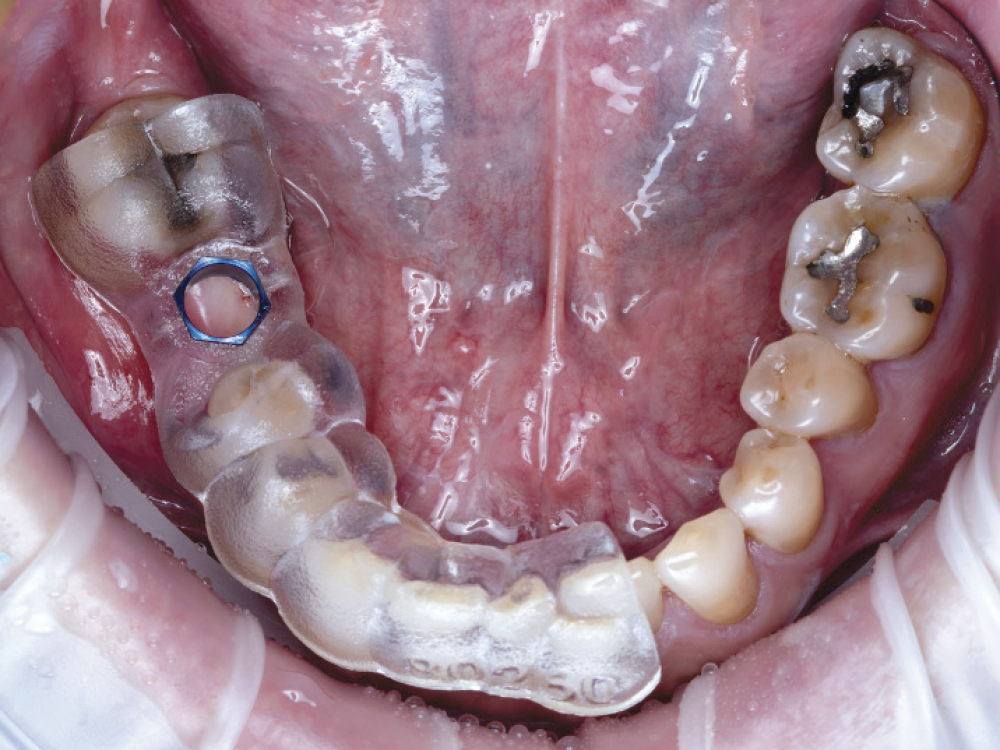

Occlusal View Which Indicates the Placement of the Surgical Guide

Figures 5a, 5b: An occlusal view clearly indicated the placement of the surgical guide and confirmed the trajectory the implant would follow as well as the position of the access hole on the occlusal surface. The detailed surgical report included a cross section revealing the implant’s proximity to vital structures. I could see the outline of the crown, the access channel, the outline of the implant (in blue), and the inferior alveolar nerve canal (in purple). I noted the distance between the implant and the nerve canal as well as the lingual concavity, another very important landmark when placing implants. To avoid complications, the plan maintained a safety zone of at least 2 mm.